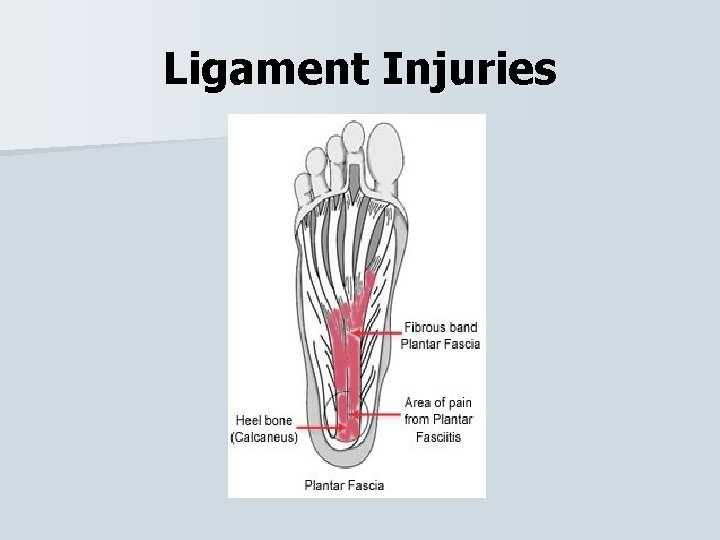

Ligament Injuries Plantar Fasciitis • The plantar surface of the foot has a thick layer of fascia that becomes injured from chronic stress. • It begins with tenderness at the bottom of the calcaneus and progresses to the toes. • Some cases the plantar fascia pulls on the calcaneus and causes a heel spur.